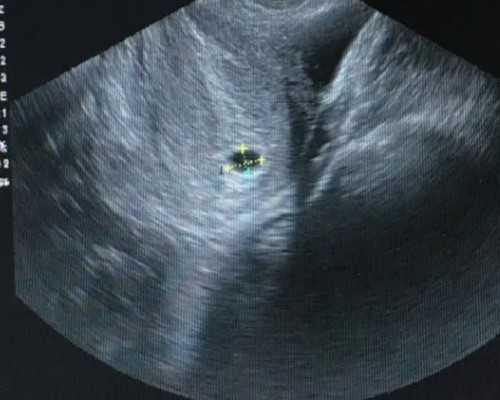

出现血HCG值偏低,隔天再次进行检查,如果上涨的次数没有翻倍,需在45天时做B超检查,以确定是否为宫内妊娠。

发现hCG低,并不一定意味着宫外妊娠或是先兆流产,因此不能盲目开始用药,需要结合孕酮值、B超进行分析,判断胚胎的存活情况和着床位置。孕早期较难准确判断。一般在6周后,再经由B超判断胚胎着床的部位是在宫内还是宫外,具体寻求医生的帮助。